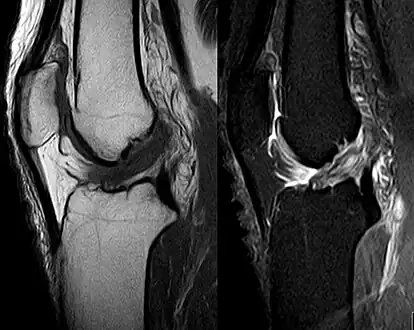

Medical imaging

Though clinical examination in experienced hands can be accurate, the diagnosis is usually confirmed by magnetic resonance imaging, which provides images of the soft tissues like ligaments and cartilage around the knee.[1] It may also permit visualization of other structures which may have been coincidentally involved, such as the menisci or collateral ligaments.[29] An x-ray may be performed in addition to evaluate whether one of the bones in the knee joint was broken during the injury.[9]

MRI is perhaps the most used technique for diagnosing the state of the ACL, but it is not always the most reliable technique as the ACL can be obscured by blood that fills the joint after an injury.[30]

-

Negative lateral inclination angle (Â) of patella in right knee with ACL injury and positive angle in normal left knee. -

Anterior cruciate ligament tear seen on MRI. T1 left, right PDW.